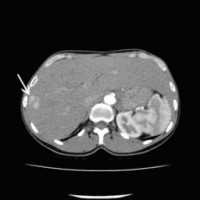

« Zurück Computertomographische Dokumentation der Embolisateinlagerung innerhalb des Tumors nach transarterieller Chemoembolisation (TACE) (Bild 2 von 5) Vorwärts »